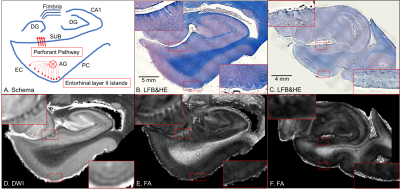

Keywords: Neurodegeneration, Diffusion Tensor Imaging Women undergoing hysterectomy with oophorectomy have an increased risk of Alzheimer’s disease. However, postoperative neuroimaging data on pathogenic processes in the brain are limited. This study was aimed to investigate the potential effect of ovariohysterectomy on brain integrity in the rat model using diffusion tensor imaging technique. Compared to the control group, the ovariohysterectomy group showed significantly lower fractional anisotropy in the corpus callosum, bilateral striatum, and bilateral cortex, suggesting neuronal injury in ovariohysterectomized rats. Therefore, neuroimaging should be performed to monitor brain alterations in women after hysterectomy with bilateral oophorectomy in clinical settings. |